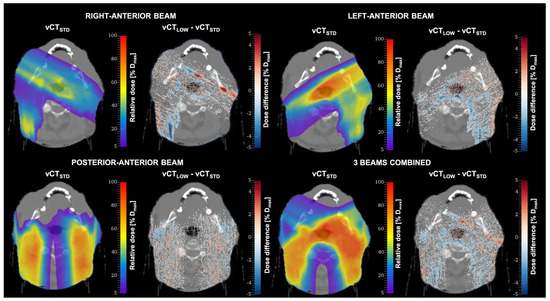

| Beam | Mean (%) | Min–Max (%) |

|---|---|---|

| Posterior-Anterior | 99.99 | 99.96–100.00 |

| Left-Anterior | 99.98 | 99.94–100.00 |

| Right-Anterior | 99.98 | 99.93–100.00 |

| Combined | 99.99 | 99.96–100.00 |